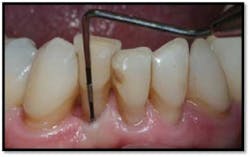

#18 buccal reflected in a mirror. Now probes 2mm reduced from 9mm